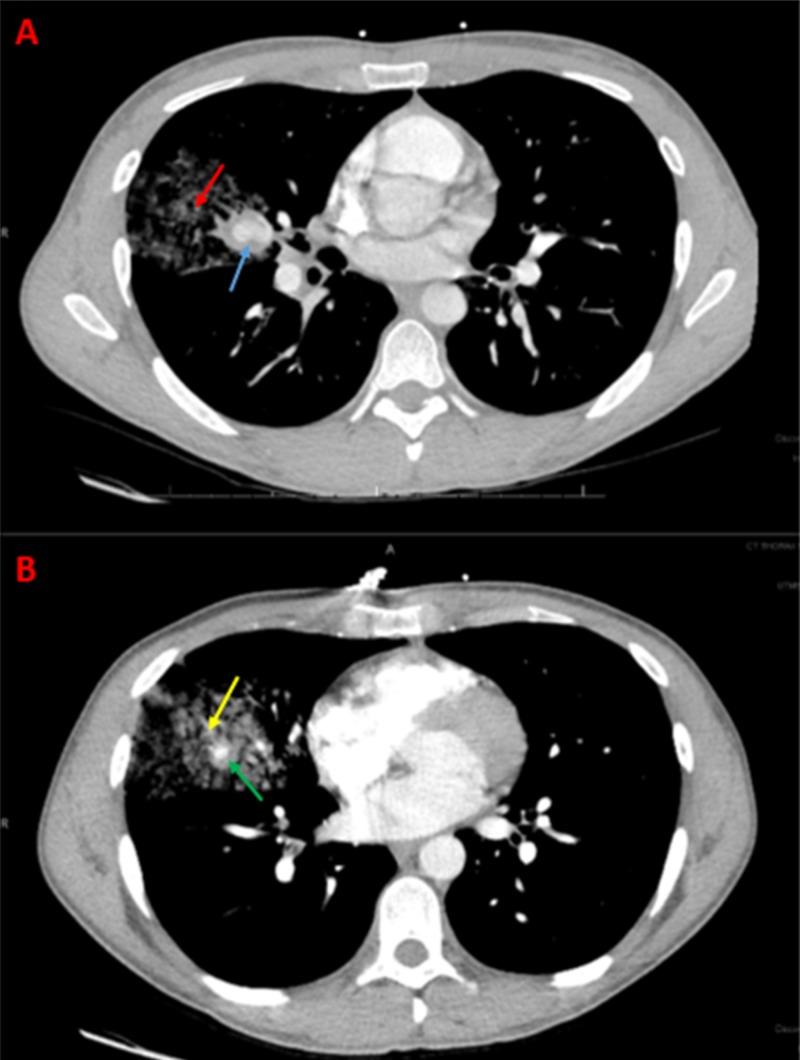

Behcet's disease is inflammatory vasculitis that has a high incidence of mortality in patients with pulmonary artery aneurysm (PAA) formation. Traditionally, patients with Behcet's disease and PAA rupture undergo invasive surgical management. Surgical intervention; however, has been shown to have high complication, failure, and mortality rates. It has become a more contemporary practice to utilize the interventional embolization of pulmonary artery aneurysms (PAAs) in patients with Behcet's disease and other various etiologies because of its inherent minimally invasive nature and decreased risk for complications. The management paradigm for treating PAAs has shifted toward endovascular embolization even in severe or emergent cases where surgical management was once thought to be the standard. The following case is a testimony to the practicality of interventional embolization in the setting of a symptomatic patient presenting with PAAs.

白塞病是一种炎症性血管炎,在形成肺动脉瘤(PAA)的患者中死亡率很高。传统上,白塞病合并PAA破裂的患者接受侵入性手术治疗。然而,手术干预已被证明具有高并发症、失败率和死亡率。由于其固有的微创性质和较低的并发症风险,对患有白塞病和其他各种病因的患者采用肺动脉瘤(PAA)介入栓塞已成为一种更现代的做法。即使在曾被认为手术治疗是标准的严重或紧急情况下,治疗PAA的管理模式也已转向血管内栓塞。以下病例证明了介入栓塞在有症状的PAA患者中的实用性。